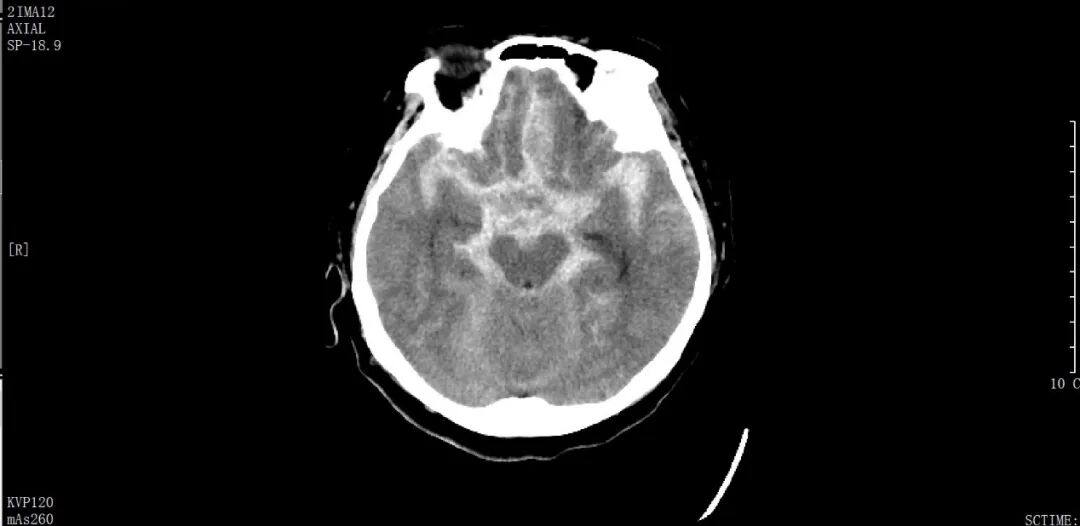

家人緊急將其送醫(yī)救治,經頭部CT診斷顯示為頸內動多個脈瘤破裂伴蛛網膜下腔出血,此外,因為發(fā)病時嘔吐及意識喪失,嘔吐物經由氣道進入了肺部,導致了吸入性肺炎。